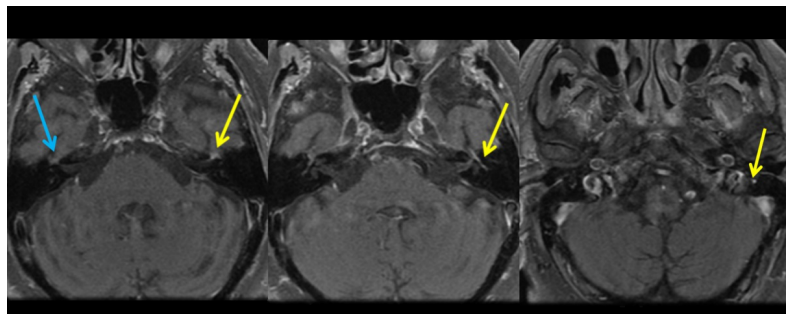

图7,施万细胞瘤,还是膝状神经节和迷路段受累

图8,T1增强,Bell麻痹患者,左侧面神经颅内段、迷路段、膝状神经节、鼓室段、迷路段较对侧均明显增强

图9,T1增强,中枢神经系统淋巴瘤,右侧面神经颅内段异常强化(终于不是迷路段和膝状神经节了)